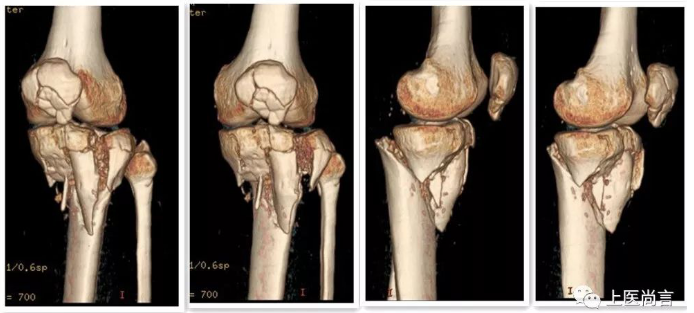

手术前CT片

患者张先生,今年42岁,因“车祸致伤左小腿4小时于2018年9月17日收住入院。入院检查后诊断为左胫腓骨多发骨折并腓总神经损伤、左髌骨粉碎性骨折、左跟骨粉碎性骨折,由于骨折部位较多,骨折较为粉碎多为体积较小的碎骨快,复位极其困难,若采用传统内固定手术可能影响关节骨折复位,增加手术后并发症风险,必然会大大增加患者的痛苦。

针对患者具体病情,云县人民医院骨科二病区决定发挥数字骨科优势,邀请到昆明医科大学附属延安医院骨科主任熊鹰及创新与转化3D打印研究中心,根据患者骨关节形态通过精密计算,按1:1比例打印出胫骨平台骨折模型,根据3D打印立体模型制订了周密的手术方案,手术前就准确定位了内固定物的形态及安放位置。